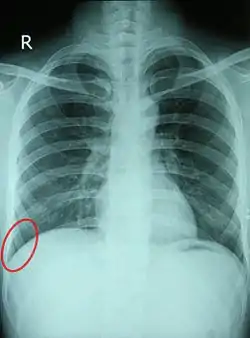

![]() Chest X-ray of a 30-year-old healthy man, with the costodiaphragmatic recess label in red ellipse | |

In anatomy, the costophrenic angles are the places where the diaphragm (-phrenic) meets the ribs (costo-).

Each costophrenic angle can normally be seen as on chest x-ray as a sharply-pointed, downward indentation (dark) between each hemi-diaphragm (white) and the adjacent chest wall (white). A small portion of each lung normally reaches into the costophrenic angle. The normal angle usually measures thirty degrees.